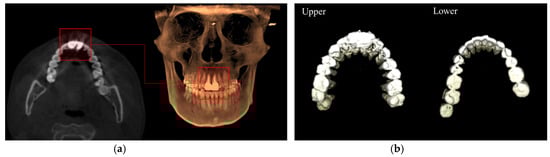

3.1. 3D Upper and Lower Teeth Segmentation from CBCT Data

3.2. Teeth Segmentation from the Scan Images of Plaster Dental Models